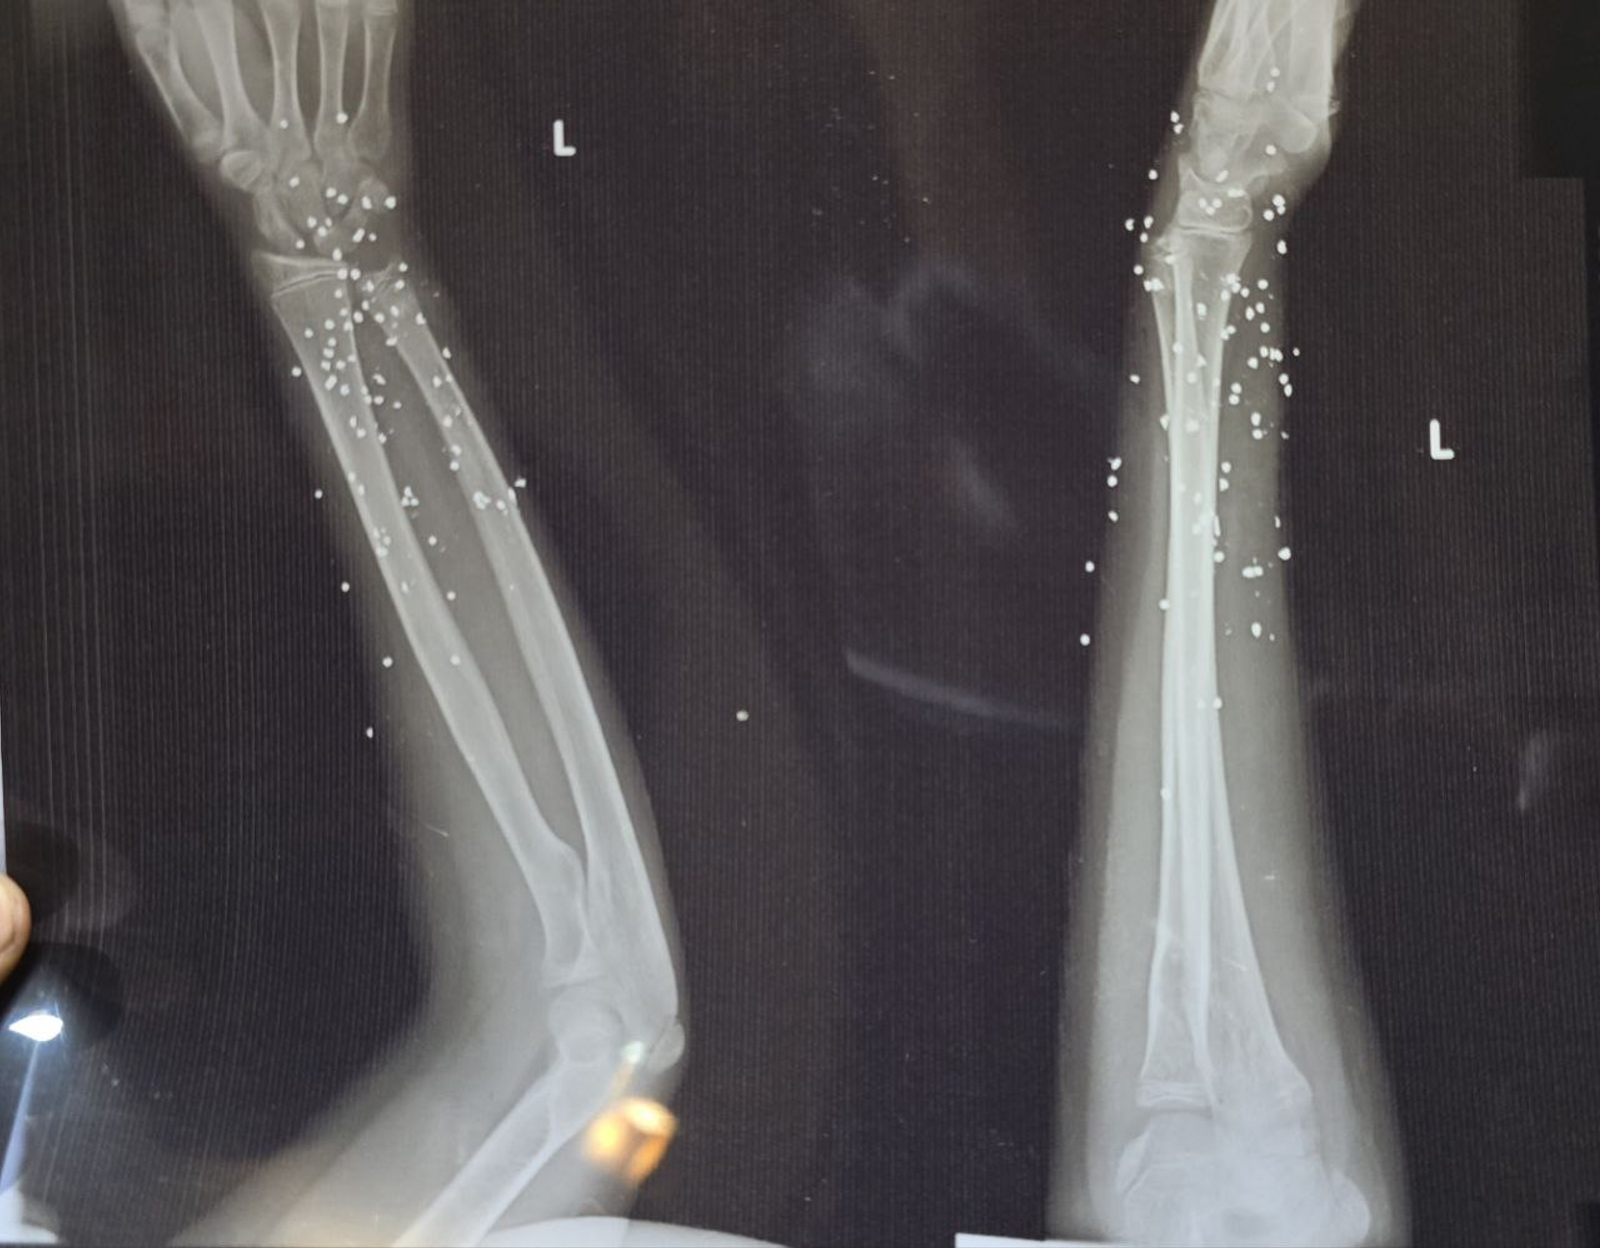

به گزارش روزنامه گاردین، بررسی ده‌ها تصویر پزشکی ثبت‌شده در جریان سرکوب اعتراضات در ایران نشان می‌دهد معترضان با ساچمه‌های فلزی و گلوله‌های کالیبر بالا هدف قرار گرفته‌اند. تصاویری که به گفته کارشناسان، از شدت جراحات و الگوی اصابت به نواحی حیاتی بدن حکایت دارند.

تصویر او یکی از بیش از ۷۵ مجموعه تصویر پزشکی شامل رادیولوژی و سی‌تی‌اسکن است که از یک بیمارستان در یکی از شهرهای بزرگ ایران به دست آمده و در اختیار گاردین قرار گرفته است. تصاویری که در طول یک شب و هم‌زمان با سرکوب اعتراضات دی‌ماه ثبت شده‌اند.

تصاویر، روایتی از شدت خشونت علیه معترضان و رهگذران ارائه می‌دهند.

ساچمه‌هایی که می‌توانند مرگبار باشند

ایران از معدود کشورهایی است که نیروهای امنیتی آن از ساچمه فلزی علیه شهروندان و برای سرکوب معترضان استفاده می‌کنند. هرچند هر ساچمه به‌اندازه گلوله جنگی قدرت تخریب ندارد، اما تعداد زیاد آن‌ها می‌تواند آسیب‌هایی بسیار شدید ایجاد کند.

گاردین در گزارش خود تاکید کرد که در برخی تصاویر، تنها یک یا دو ساچمه در جمجمه دیده می‌شود که پس از عبور از چشم در حفره آن متوقف شده‌اند.

در موارد دیگر، صدها ساچمه در بدن پراکنده شده و بافت نرم را تخریب کرده‌اند.

گلوله‌های تمام‌فلزی

در ۹ بیمار، گلوله‌های کالیبر بالا همچنان در بدن باقی مانده و در تصاویر دیده می‌شوند.

در موارد دیگر، مسیر شکستگی استخوان و قطعات فلزی باقی‌مانده نشان می‌دهد احتمالا اصابت گلوله‌های پرسرعت، عامل جراحت بوده‌اند.

کارشناسان این مهمات را از نوع «تمام‌فلزی» معرفی کرده‌اند؛ گلوله‌هایی که معمولا با سلاح‌هایی مانند ای‌کی-۴۷ (AK-47) شلیک می‌شوند و شکل خود را حفظ می‌کنند.